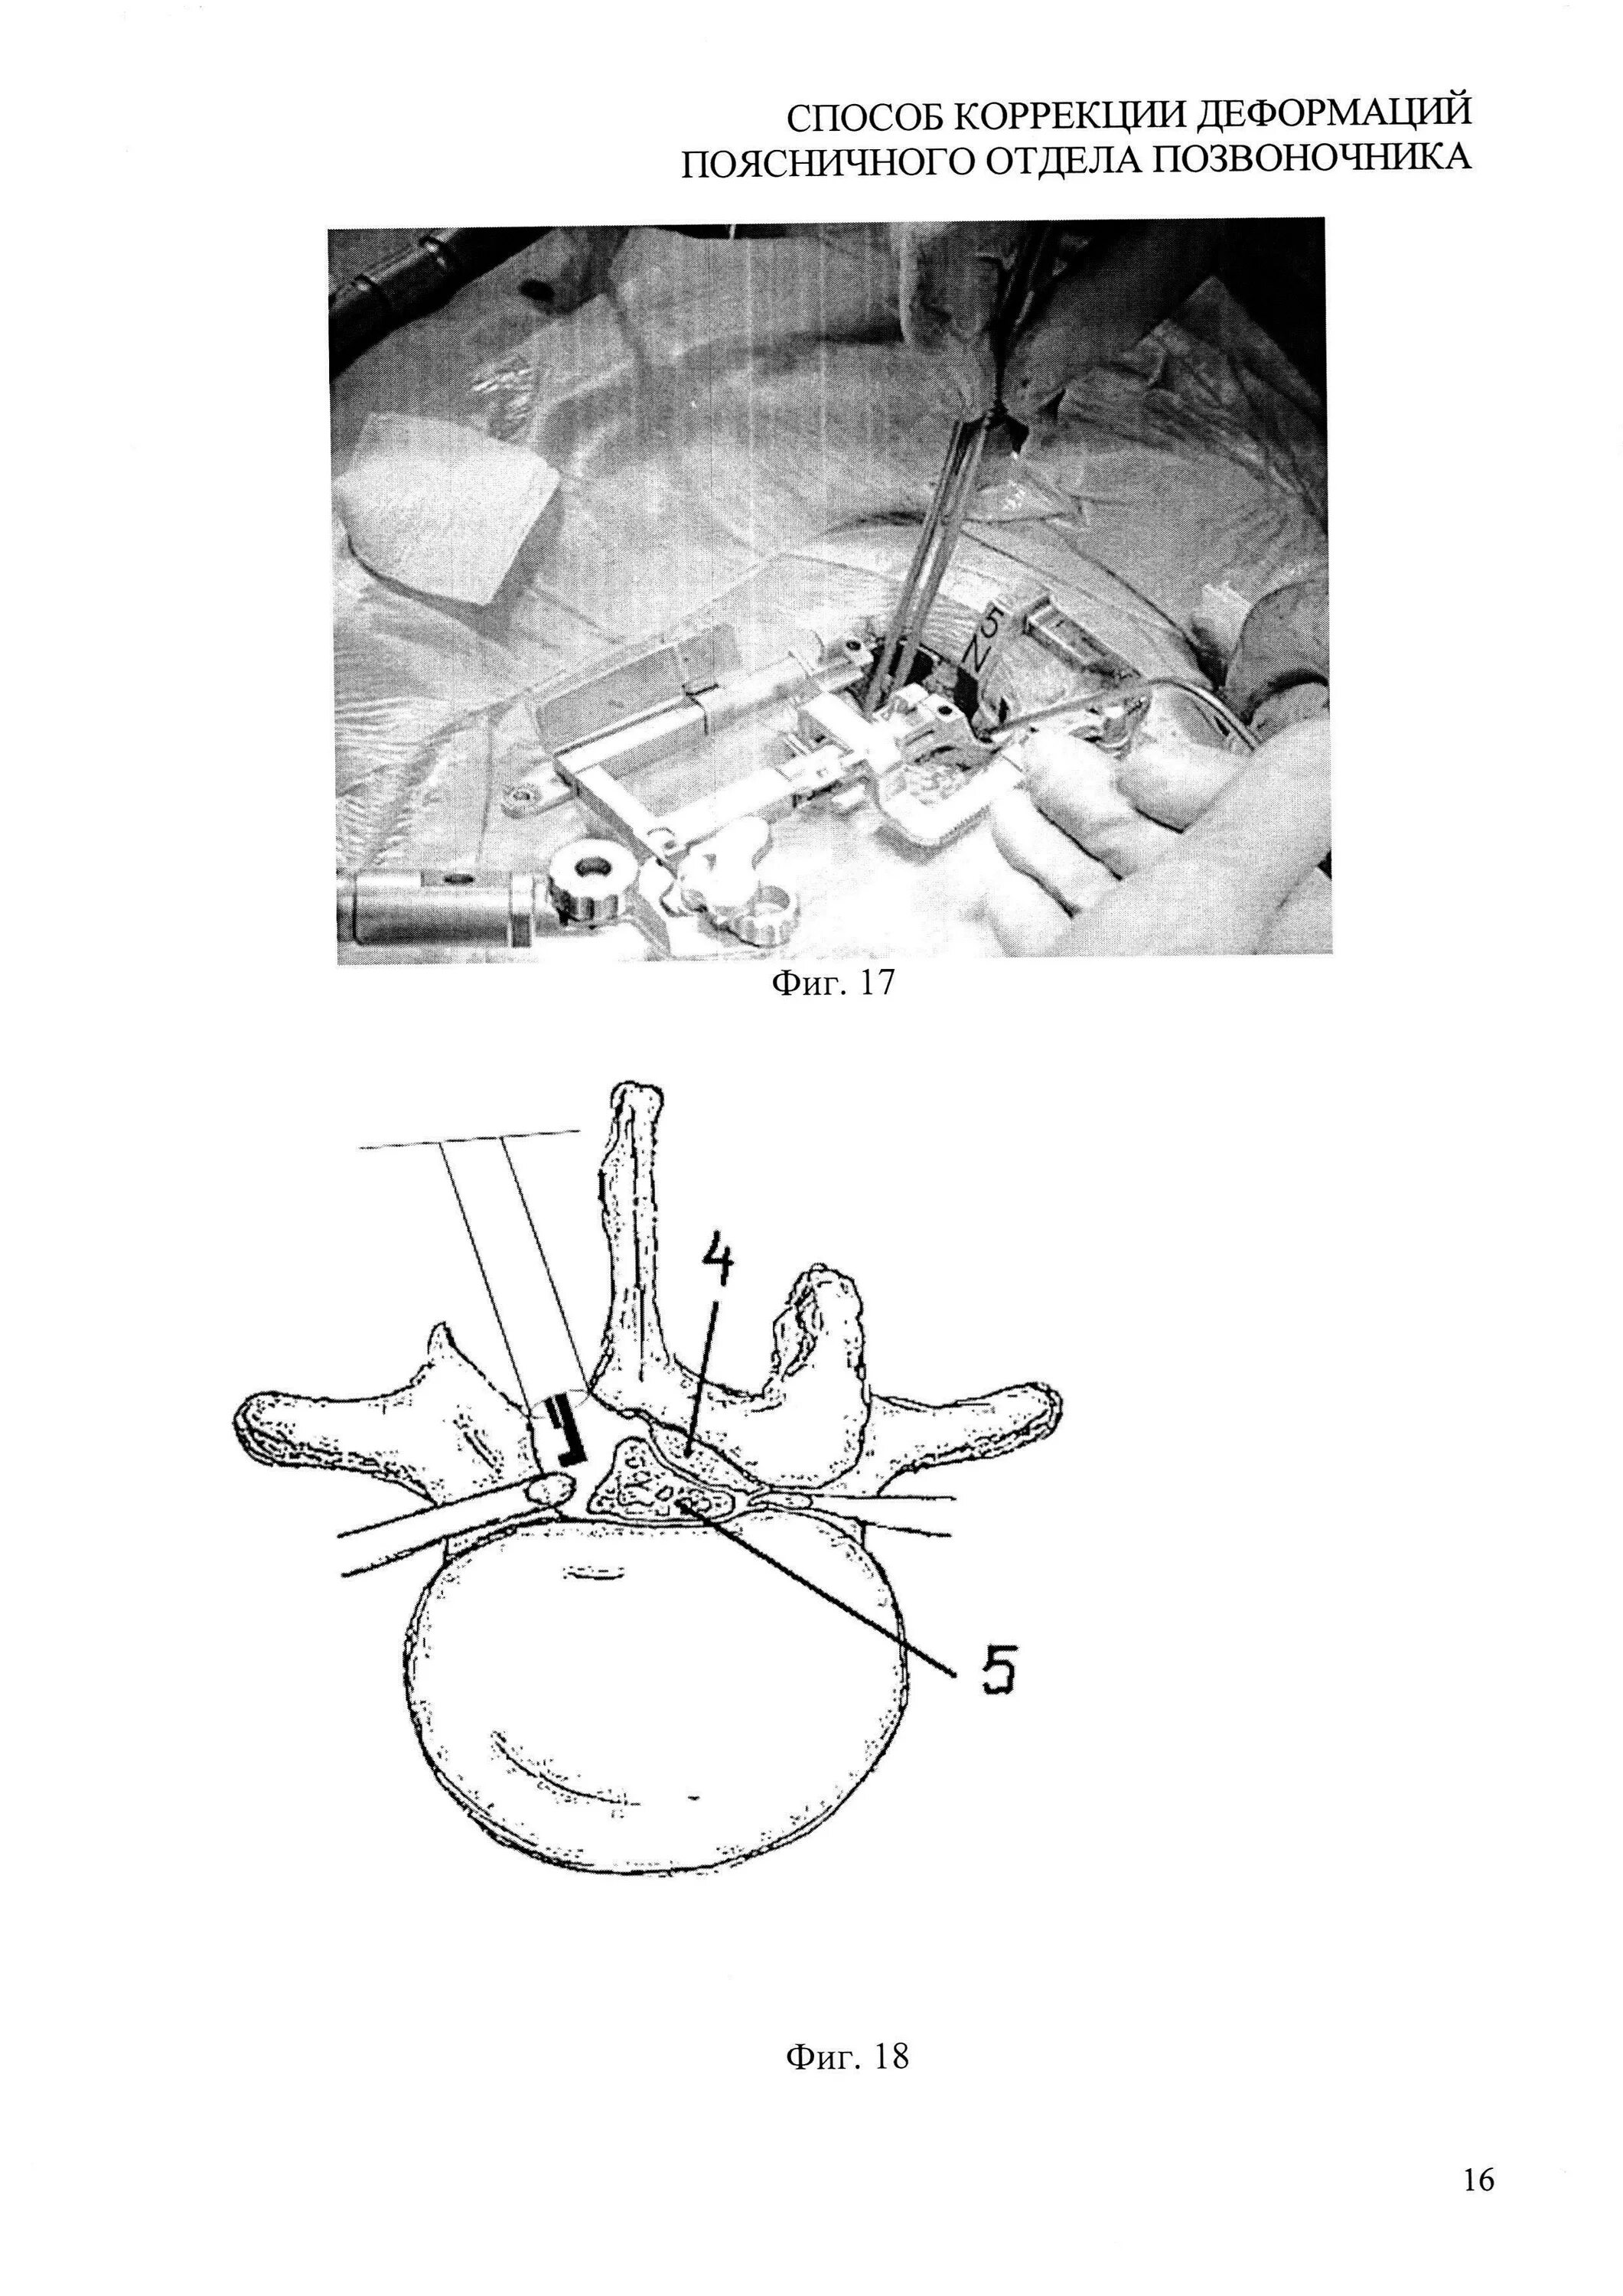

Деформация дурального мешка поясничного